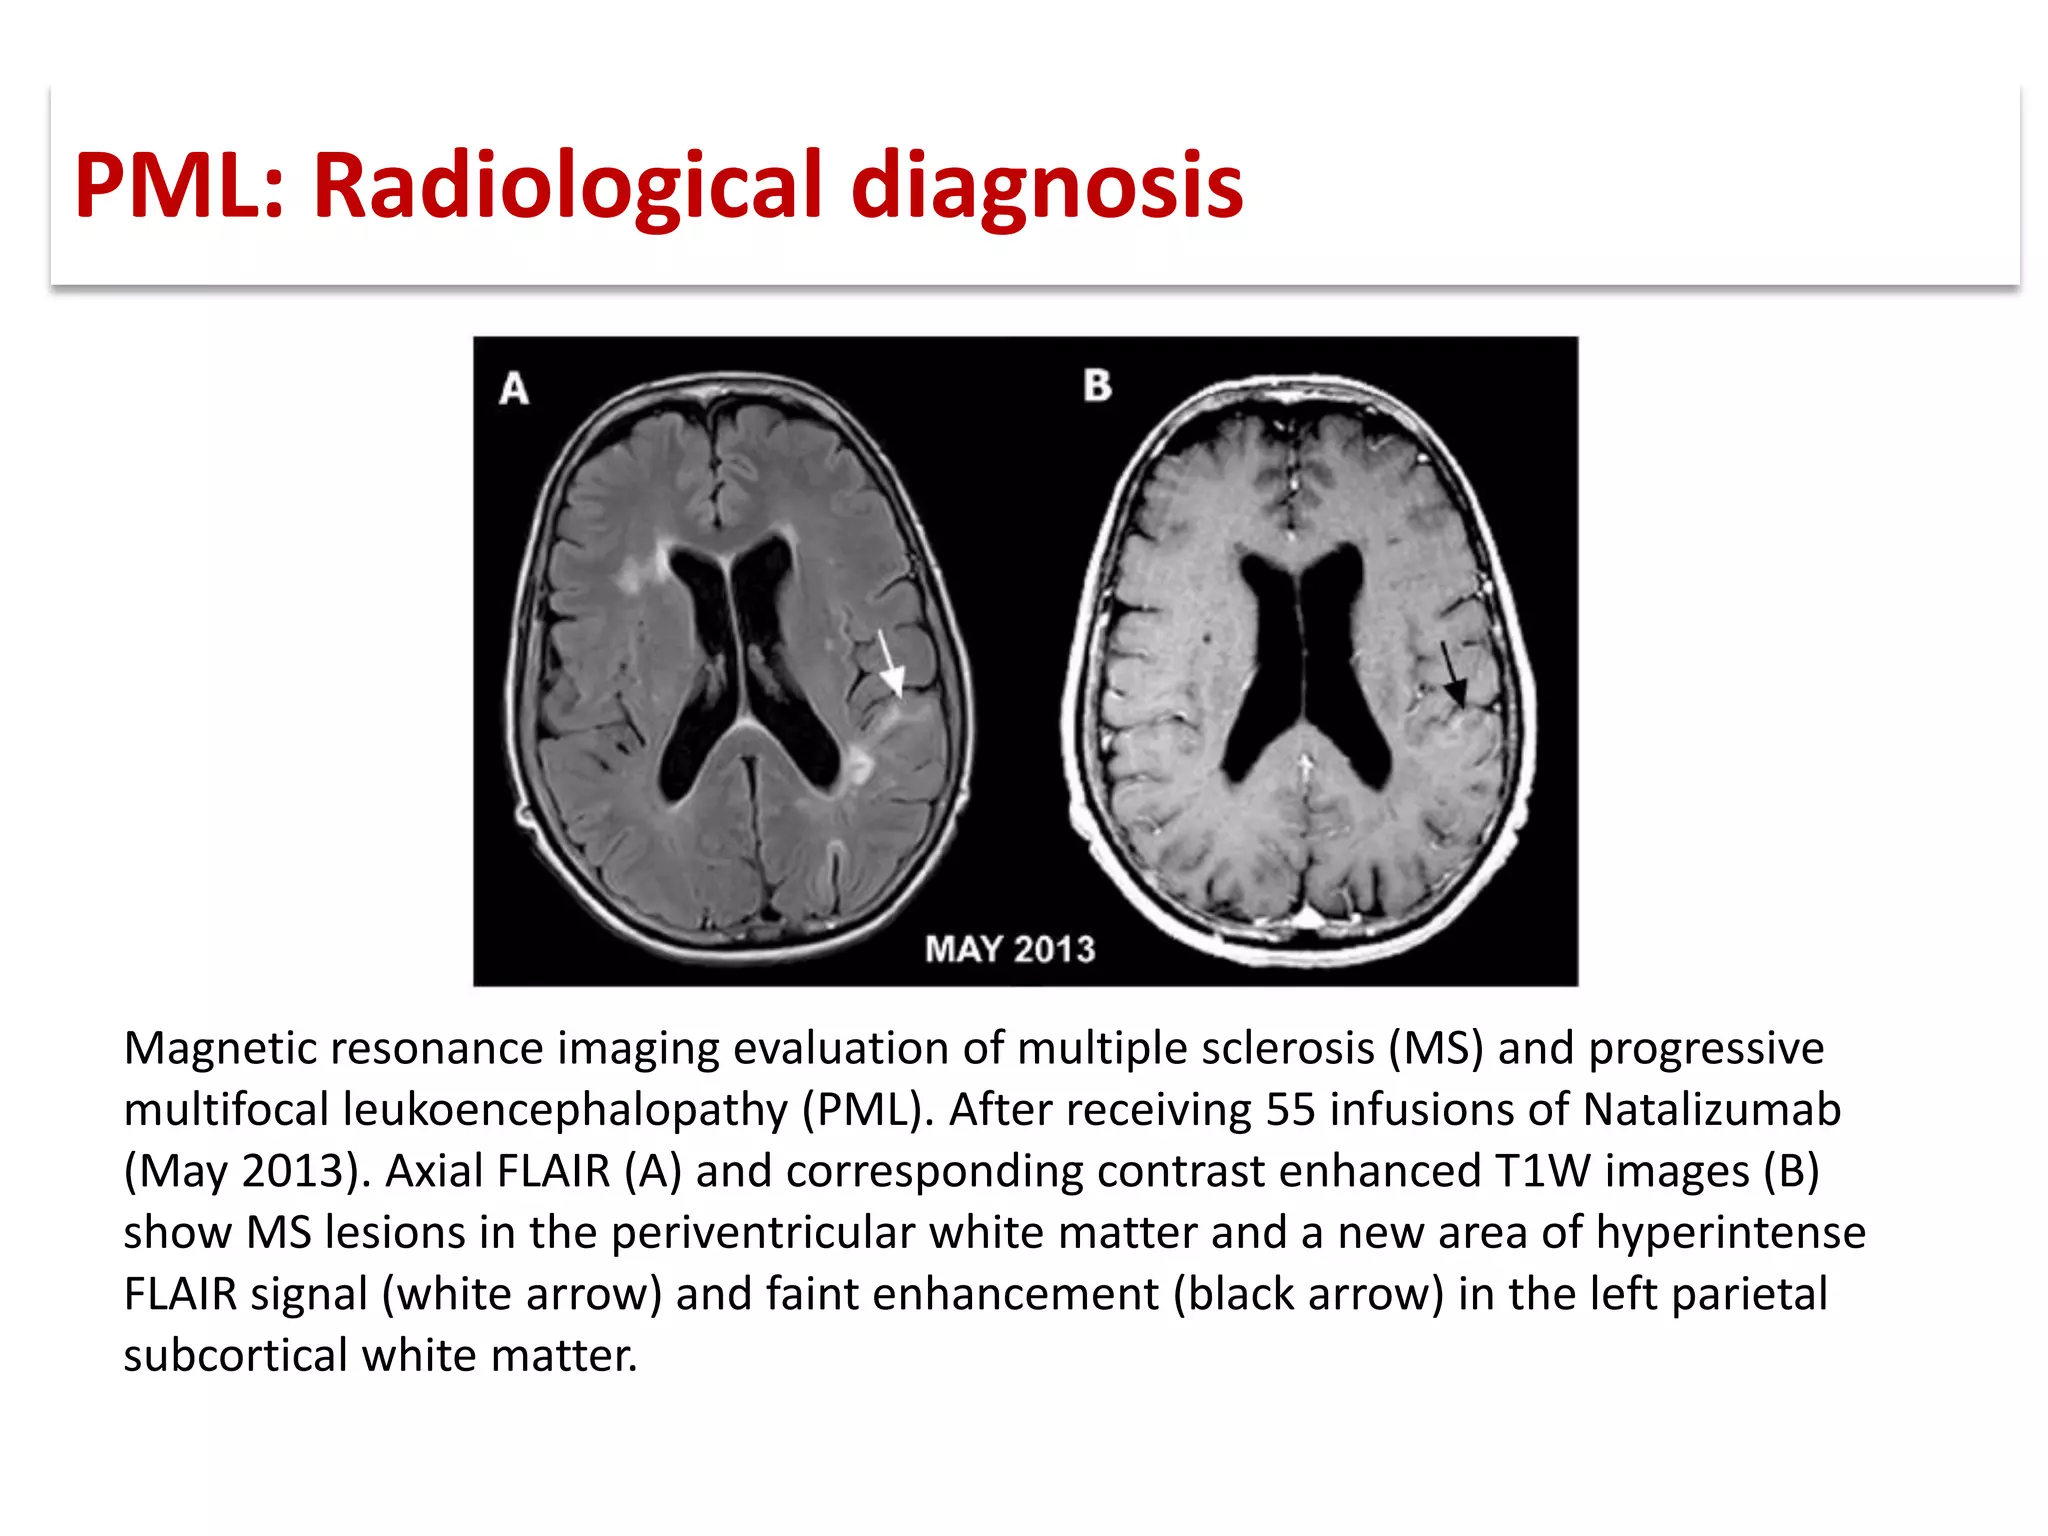

This document discusses progressive multifocal leukoencephalopathy (PML), an opportunistic infection caused by the John Cunningham virus (JCV) that leads to demyelination in the central nervous system. It highlights the epidemiology, clinical manifestations, diagnostic methods, and risk factors associated with PML, particularly in immunocompromised patients and those undergoing immunomodulatory therapies. It also presents data on the incidence of PML in patients treated with natalizumab and other therapies, addressing the relationships between these treatments and the development of PML.